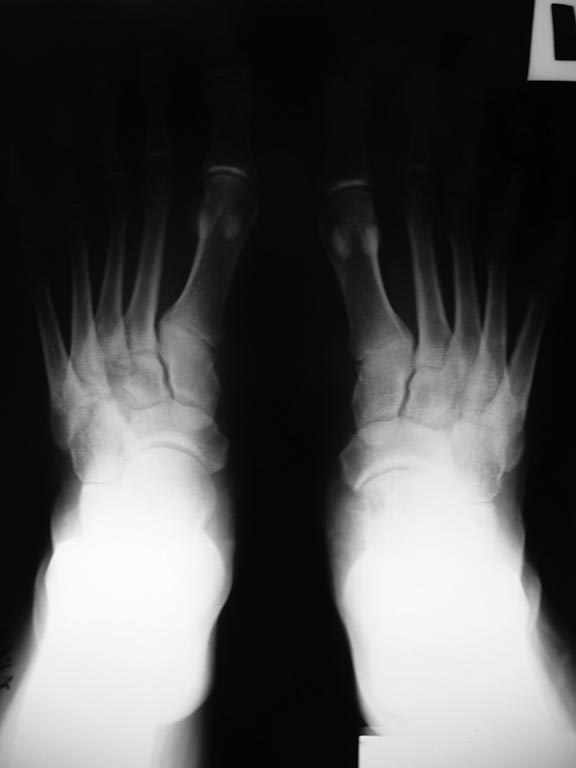

Здравствуйте, глубокоуважаемые участники форума. Прошу Вас о помощи в , на наш взгляд, не простом случае заболевания среднего отдела стопы у ребёнка 16 лет. Девушка имеет солитарную кисту головки и шейки таранной кости стопы. Обратилась и госпитализирована с болями в среднем отделе стопы.

Ребёнок 16 лет. Направляющий диагноз: "Солитарная киста головки и шейки таранной кости стопы".Гистологический диагноз выставлен на основании пункционной биопсии в одной из авторитетнейших онкологических клиник Москвы. Выполненное лечение - инъекция Коллатампа - апрель 2017г. .

Ходит без ортеза. Жалуется на боли в области Шопарова сустава. Свод стопы сохранён. Тест "на носочках"-выполняет 15-20 секунд, жалуясь на возрастающие боли. Походка не нарушена. Может пройти 1 км пешком. Девушка крупного телосложения. Атрофии мышц голени нет. Пальпаторно - болезненность в области тыльной поверхности стопы в таранно-ладьевидного сустава. Движения в голеностопном суставе - в полном объёме. Результаты исследований будут в приложениях.

Вероятнее всего больной можно будет помочь исключительно оперативным лечением. Наше предложение:откртытая экскохлеация полостей кисты, ауто- или аллопластика аллографтами, резекция и атродезирование таранно-ладьевидного сустава, : пластина таран-ладья и винты Herbert, разгрузка на 2-3 мес, стелька компенсирующая.

Вопрос к коллегам: целесообразно ли такое вмешательство?Следует ли решать проблему одной операцией - пластика и артродез сразу? Или артродез можно отложить, надеясь на компенсаторные возможности?

Насколько операция рациональна сейчас? Если артродез - то всего Шопарова сустава?

Как поступить с пластикой кисты тарана? Чем? Алло- или ауто? Доступны TUTOGEN и Силариф.

Следуетли комбинировать остесинтез пластиной и винтами - в какой последовательности синтезировать? Следует ли выполнять компенсирующую абдукцию стопы в данном случае? Заранее спасибо за ответы. С глубоким уважением.